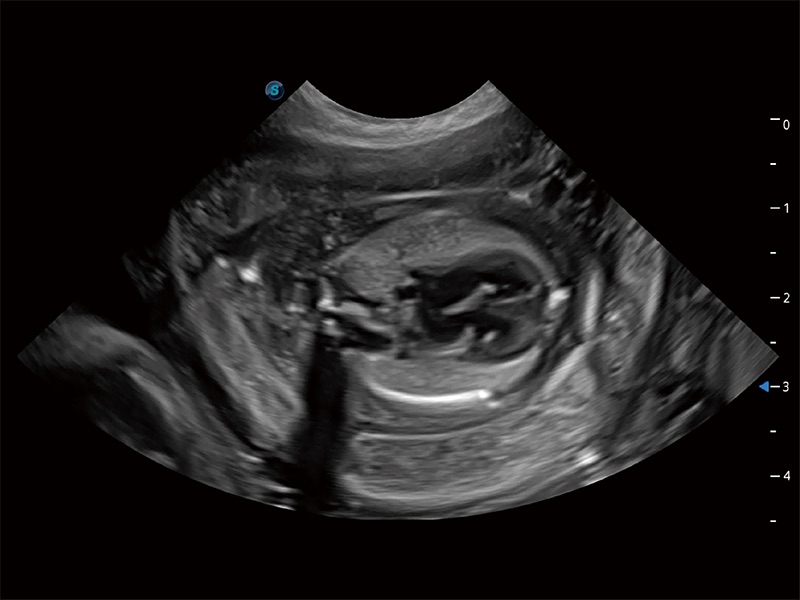

ProPet 80 專為動(dòng)物醫(yī)生設(shè)計(jì),對(duì)不同的動(dòng)物體型和生理結(jié)構(gòu)作出了針對(duì)性的優(yōu)化。通過(guò)動(dòng)物影像專用軟件,可滿足個(gè)性化的應(yīng)用需求,幫助動(dòng)物醫(yī)生獲得更精確的診斷數(shù)據(jù)。

為精細(xì)結(jié)構(gòu)及組織邊緣提供高清晰度的圖像和更大的成像視野。幫助減輕醫(yī)生的用眼疲勞,快速精準(zhǔn)獲得測(cè)量的數(shù)據(jù)。

ProPet 80 全新的動(dòng)物超聲智能軟件和豐富的探頭群,為動(dòng)物醫(yī)生提供了高清晰度和精細(xì)分辨率的圖像,無(wú)論在寵物、馬科、畜牧還是實(shí)驗(yàn)室動(dòng)物等應(yīng)用中都可以輕松應(yīng)對(duì),為您的日常工作帶來(lái)滿意的體驗(yàn)。